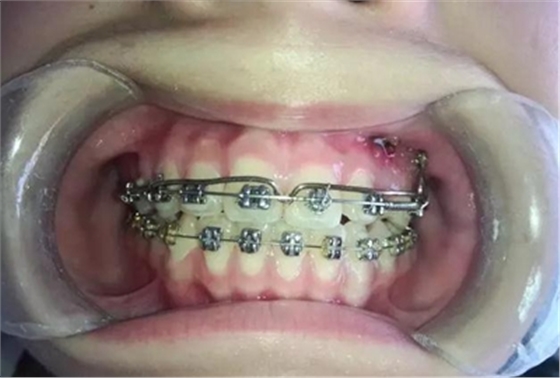

牽引了三四個月尖牙終于長出來了,也遠離了側(cè)切牙

當尖牙到達了指定位置后,又采用了主弓絲和附弓絲,主弓絲采用了不銹鋼絲方絲,有效的避免了反作用力引起相鄰的牙齒出現(xiàn)小開合, 維護牙弓形態(tài)。

主弓絲和輔弓絲的結(jié)合使用,可以有效避免出現(xiàn)小開合,同志們一定要注意啊!